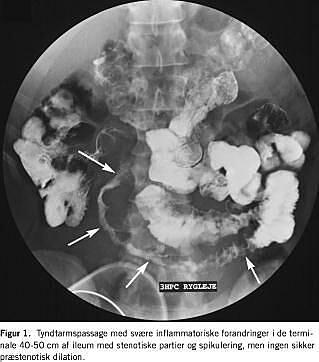

En 21-årig, tidligere rask mand blev indlagt efter tre ugers smerter i højre fossa, smerterne var accentueret gennem den seneste uge. Patienten havde kvalme uden opkastninger, og han havde normal afføring. I samme periode havde han vekslende artralgier. Der var ingen rejseanamnese. Objektivt fandt man, at patienten var subfebril, abdomen var diffust øm med slipømhed nedadtil i højre fossa. Der blev fundet normale forhold ved en rektaleksploration. En ultralydundersøgelse af abdomen viste flere dilaterede tyndtarmssegmenter i højre fossa. Infektionsparametre viste leukocyttal på 14,5, c-reaktivt protein (CRP) på 41 og orosomucoid på 44. en urinstik viste 3+ blod, 1+ protein. Creatininværdien var normal. Urin- og faecesdyrkning var negativ. Tyndtarmspassage viste svære inflammatoriske forandringer i den terminale ileum med stenotiske partier og spikulering, men ingen sikker præstenotisk dilation (Figur 1). På formodning om mb. crohn blev patienten behandlet med mesalazin.